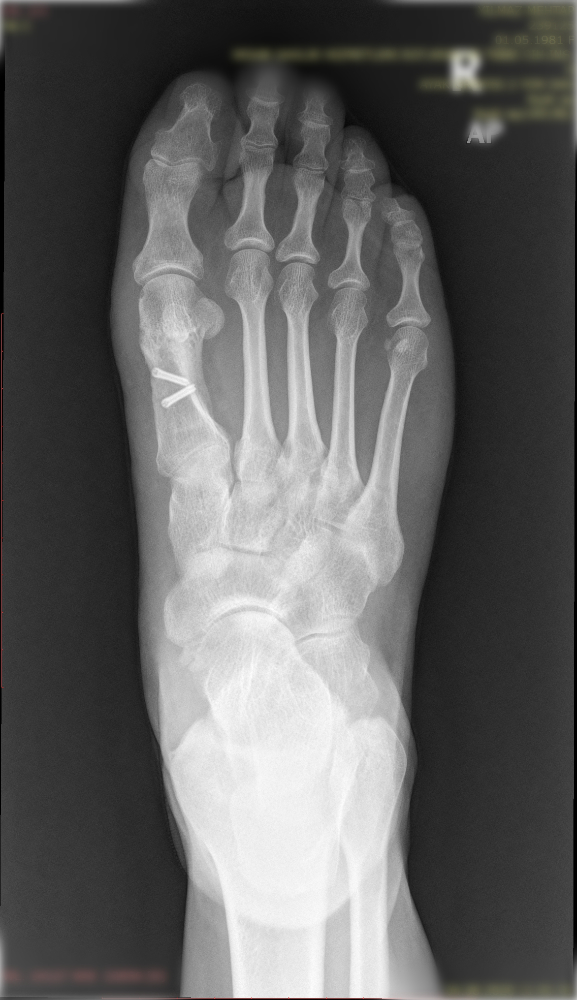

Halluk valgus ayak baş parmağının zaman içerisinde değişik nedenlerle eğilmesi ile ayak yan tarafında çıkıntının da eşlik ettiği bir rahatsızlıktır. Sıklıkla bayanlarda görülmesine rağmen erkeklerde ve çocukluk yaşlarında da karşılaşılmaktadır. Ayağın yan tarafında olan çıktı ve baş parmağın diğer parmakları itmesi ile ayakta şekil bozukluğu ve ağrı oluşur. Bu şekil bozukluğu kişinin ayakkabı giymesinde sıkıntılara neden olabilir.

Tedavisinde ayağın yük veriri pozisyonda çekilen grafileri üzerinde yapılan ölçümlerden sonra hastanın yaşı ve aktivite seviyesine göre kişiye özel planlanmaktadır. Erken dönemlerde ayakkabı modifikasyonu, parmak arası makarası ve gece ateli kullanılmaktadır. Cerrahi gerekliliğe hastanın deformitesinin büyüklüğüne ve hastanın taleplerine göre karar verilmektedir.

Aşağıdaki grafiyi öncesi sonrası şeklinde görmek için farenizi sağ sola hareket ettiriniz.

Yukarıdaki grafileri daha net ve büyük görmek için üzerine tıklayabilir. Sağ üst köşedeki + - tuşları ile daha da büyütebilirsiniz.